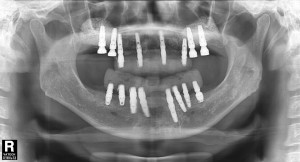

치료 중 찍은 방사선 사진입니다.

치료 필요에 따라 뼈이식도 진행하였습니다.